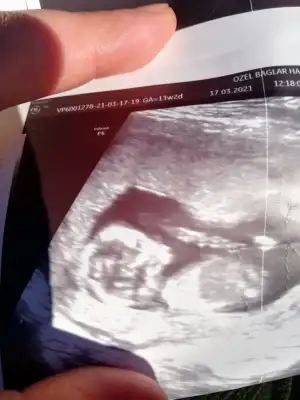

Ikra meyra Ikra meyra tahminin doğru çıktı 16 hafta erkek demiştin doktorum kesin erkek elbiselerini bile al dedi ☺ değişir mi bilmiyorum ama atıyim bir bak

Artık erkektir canım 😍 sağlıkla gelsin oğlusun 🥰 anketim oylarsaniz sevinirim 😘